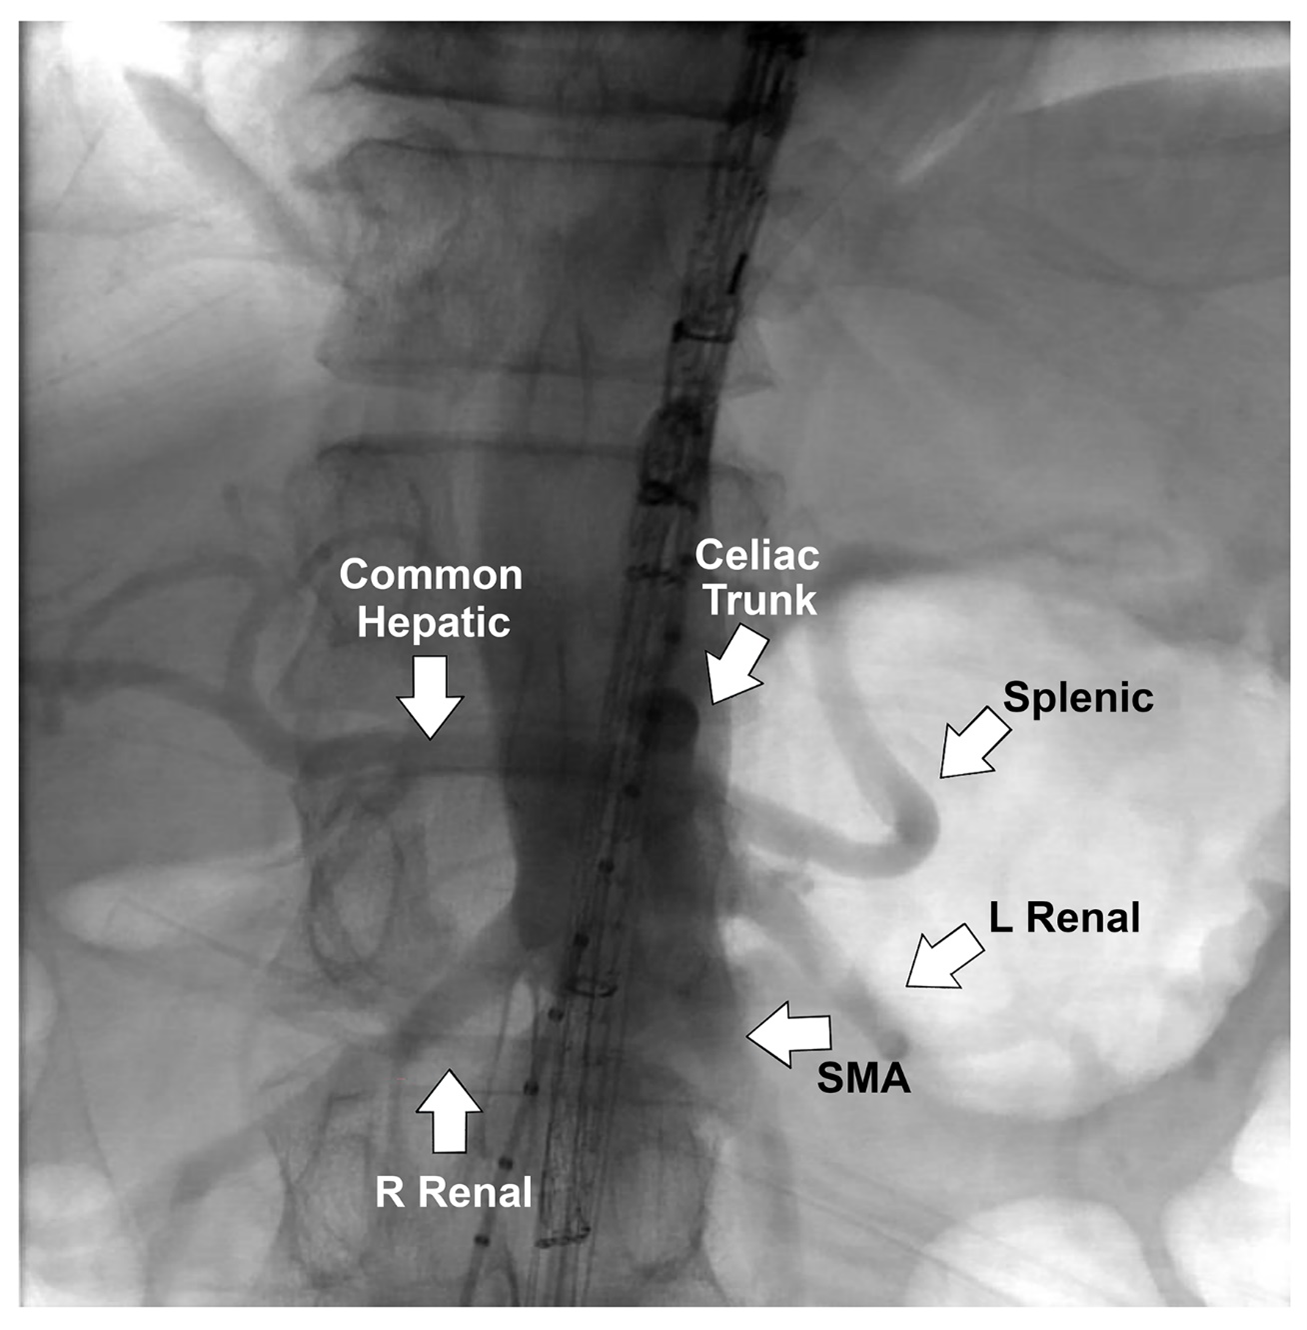

Both femoral arteries were accessed percutaneously with a Perclose device (Abbott). Left axillary artery cutdown was performed, and a 12F sheath was inserted; a 22F and a 12F sheath were deployed in the right and left femoral arteries, respectively. The TAMBE device was inserted from the right groin into the aorta and partly deployed. Using the axillary sheath, the celiac, superior mesenteric, and bilateral renal arteries were sequentially cannulated, and VIABAHN VBX stents (W. L. Gore & Associates, Inc.) were deployed. The infrarenal branch was deployed from the right groin into the TAMBE device, followed by ipsilateral limb extension from the right groin and the contralateral limb from the left groin.

CTA at completion confirmed complete exclusion of the aneurysm with preserved flow to the visceral and bilateral internal iliac arteries (Figure 3, Video 1). The total procedure time was 3 hours. The patient was discharged on the first postoperative day without complications. Two-week postoperative CTA (Video 2) confirmed patency of all target vessels and exclusion of the aneurysm sac without endoleak or migration.